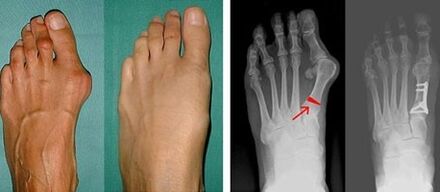

Valgus deformity of the first toe most often affects women of mature age, but it also affects men.A deformed base of the thumb does not look aesthetically pleasing.In this case, the person feels physical discomfort, and in an advanced stage – pain.Deviation of the big toe is the result of an uneven body load on the foot.Such changes have a detrimental effect on the feet and other toes.

If the visual examination and X-rays do not give any result, the patient is referred to plantography to determine possible flat feet.This method involves taking footprints, based on which shoes or insoles with orthopedic properties are made for the patient.The patient is then prescribed podometry.This method uses computer analysis to determine the pressure of a person's weight on the feet.The results of advanced diagnostics are the basis for choosing a treatment method for curvature of the first and second toes.

In the first stage of identification of valgus of the big and little toe, the doctor conducts a visual examination.In this way, it determines the stage of development of the pathology.In order to determine detailed changes in the joints, X-rays and plantography are prescribed.